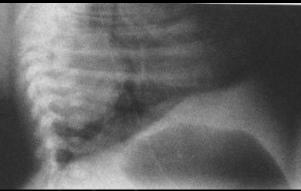

Image

radiologique de atresia congenitale de type I . La

contrast arrete a D4 sur la bifurcation de

trachee |

|

Un sonde radio-opaque bute dans oesophage

se donne la cite de atresia . Cliche

thoracoabdominale de face . |